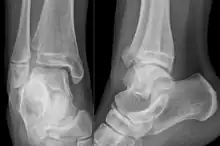

Sur les radiographies, on peut voir une fracture de la malléole médiale, de la malléole latérale et/ou du bord antéro-postérieur du tibia distal. Le bord postérieur (appelé malléole postérieure) est beaucoup plus fréquemment lésé que la face antérieure du tibia distal. Si les malléoles latérale et médiale sont brisées, on parle de fracture bimalléolaire (certaines d'entre elles sont appelées fractures de Pott (en)). Si la malléole postérieure est également fracturée, on parle de fracture trimalléolaire.[réf. nécessaire]

Vue AP en contrainte manuelle montrant une déchirure du ligament deltoïde.